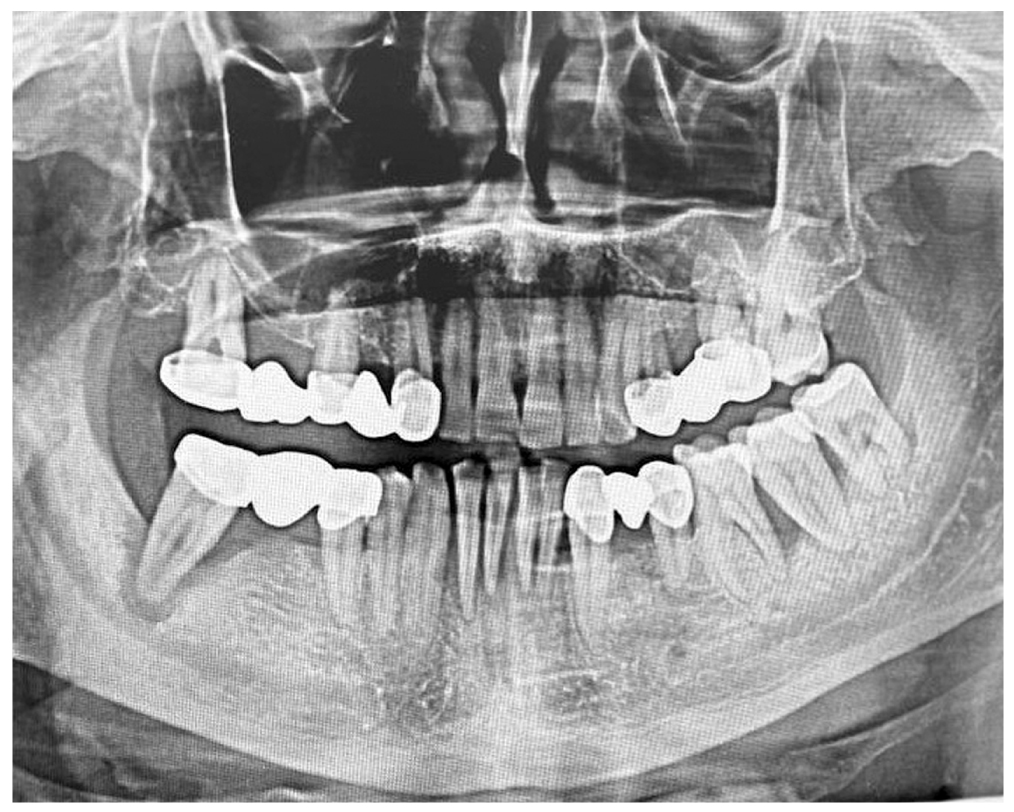

Three disease stages are known — mild, moderate and severe. The mild degree of severity is characterized by the presence of swelling, cyanotic and bleeding mucosa of the gingival margin, 1st degree loosening of teeth and by the presence of a periodontal recess up to 4 mm deep. The radiology images in cases of mild disease show dilation of periodontal fissure, loss of integrity in the cortical plate, resorption of the alveolar bone walls by 1/3 of the dental root length. In cases of moderate severity of chronic generalized periodontitis, the findings include an increase in the depth of periodontal recess up to 6 mm, pathological loosening of teeth (2nd degree) and exposition of the dental roots. The orthopantomograms from the patients with 2nd degree show resorption of alveolar bone walls, reaching up to 1/2 of the length of the dental root and showing signs of destruction in the cortical plate. The severe chronic generalized periodontitis is characterized by an increase in the pathological loosening of teeth (up to degree II or III), by dislocation of teeth, by the presence of periodontal recesses with a depth of more than 6 mm and with the presence of purulent exudate, by significant traumatic occlusion and exposition of the roots. Upon radiology examination, the findings include resorption of alveolar bone walls to a distance of more than 1/2 of the dental root length with the presence of pathological bone pockets.

The clinical signs and objective examination data in Group 2 allowed for defining the depth of periodontal recesses as reaching 6 mm, along with 2nd degree pathological loosening of teeth and exposing the dental roots. The orthopantomogram in patients from this subgroup shows a resorption of alveolar bone walls down to 1/2 of the length of dental root and destruction of the cortical plate (Fig. 3), with the mean microorganism concentration in Group 2 being increased up to 5.7±0.80 GE, which is 1.7 times higher than the same parameter in the control group (p <0.001).

Fig. 3. Orthopantomogram — patient N., aged 49 years: chronic generalized periodontitis of moderate severity degree.